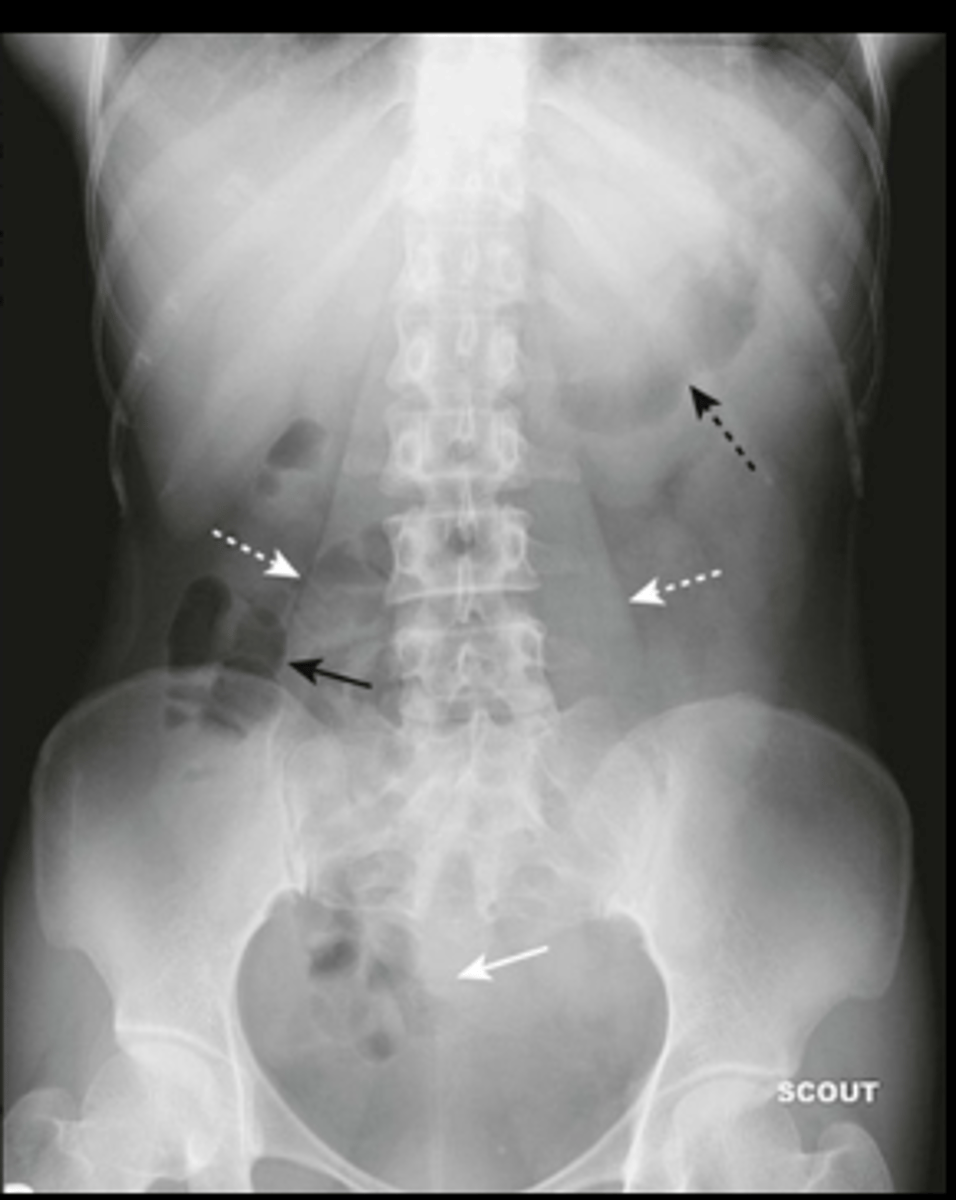

intraperitoneal air (pneumoperitoneum)

air in peritoneal cavity, caused by rupture of an air-containing loop of bowel, trauma, or abdominal surgery (5-7 days post op)

1. air beneath diaphragm

2. rigler sign- visualization of both sides of bowel wall

3. visualization of falciform ligament

hepatomegaly

enlarged liver, displacement of all bowel from RUQ down to iliac crest and across midline

splenomegaly

enlarged spleen, projects well below 12th posterior rib